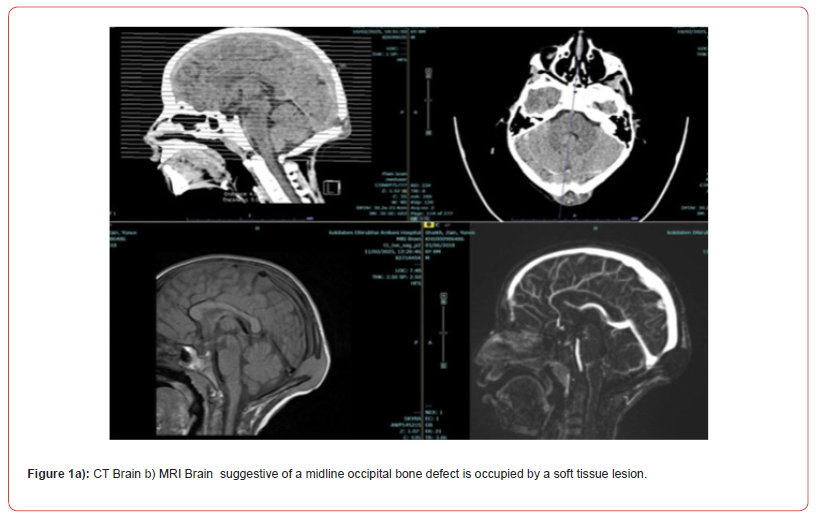

A 6-year-old child presented to the emergency department following a fall from a significant height, landing on the occipital region of the head. At the time of injury, the child was conscious and neurologically intact. A non-contrast computed tomography (CT) scan of the brain was performed, which did not reveal any acute intracranial abnormalities, skull fractures, or significant soft tissue injury. The child was managed conservatively and discharged with instructions for follow-up. Two weeks later, the patient was brought back with a gradually enlarging, non-tender swelling over the occipital region. The parents reported no fever, weight loss, or neurological symptoms, but noted that the swelling had progressively increased in size without signs of redness or warmth. On examination, the swelling was firm, fluctuant, and localized to the midline occipital region, without overlying skin changes or signs of infection. A repeat CT scan of the head, now with bone window settings, revealed a well-defined lytic lesion involving the midline occipital bone. The lesion caused cortical thinning and expansion, with a defect noted in the inner and outer tables of the skull. There was an associated soft tissue component extending extracranially, but no evidence of intracranial extension. Magnetic resonance imaging (MRI) was subsequently performed for further characterization. The lesion appeared hypointense on T1-weighted images and hyperintense on T2-weighted sequences, with no significant post-contrast enhancement. Based on the radiological features and the absence of systemic symptoms, an intradiploic epidermoid cyst was initially considered the most likely diagnosis (Figure 1a).